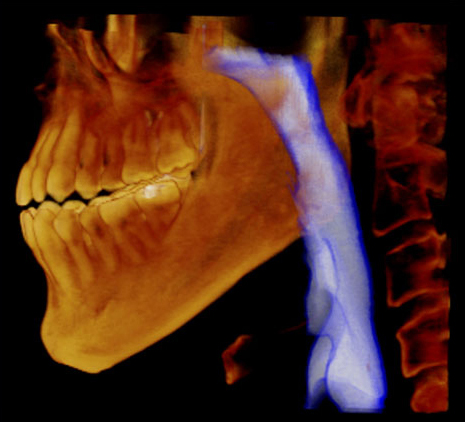

歯科用CTを用いた正確な診断

歯科用CTは、顎の骨の状態を3D画像で詳細に把握できる先進的な機器です。これにより、骨の厚さや密度を正確に確認でき、インプラント治療の計画をより精密に立てることができるため、治療の成功率を大幅に向上させます。

複雑な歯の根の状態も精密に診断できるため安全なインプラント治療に必須です。

シミュレーションソフトで事前確認

取得したCT画像をもとにシミュレーションソフトで治療計画を作成し、インプラントの埋入位置や角度を事前に確認します。このシミュレーションにより、手術の正確性が増し、歯茎を切開する範囲を最小限に抑えることが可能です。その結果、術後の治りが早まり、身体への負担も軽減されます。